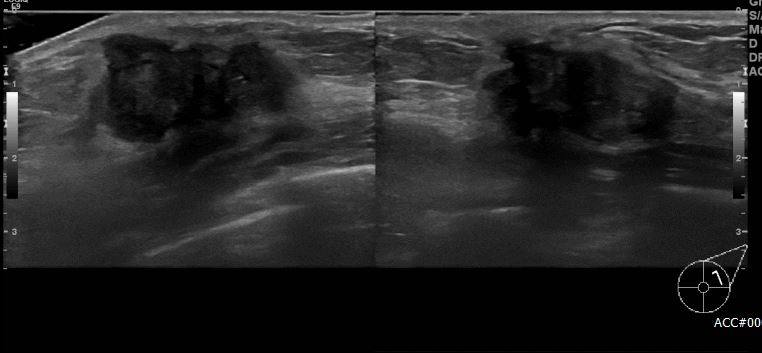

좌측 먼져지는 멍울로 내원하신 30대 여성 분으로 좌측 만져지는 멍울 조직검사 시행하여 좌측 침윤성 유관암 진단 되었습니다.